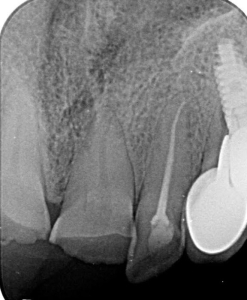

- Îndepărtarea pivoților de metal sau din fibră de sticlă:

Îndepărtarea unui pivot metalic/înșurubat devine ușoară sub microscop, prin tăiere selectivă, cu scopul de a conserva cât mai mult din structura coronară dentară.

În cazurile în care există pivoți din fibră, situația este mai complexă din cauza prezenței rășinii în interiorul canalului radicular.

Utilizarea magnificației (vizualizării mărite) poate preveni pragurile, perforațiile sau îndepărtarea excesivă de dentină în timpul demontării pivotului din fibră.